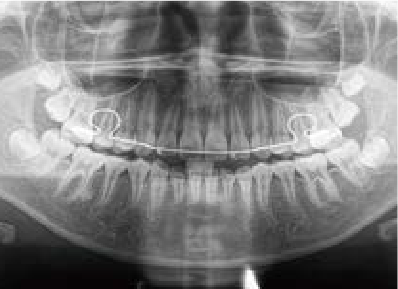

Jさん (矯正開始時:8歳)

Before

After

歯がガタガタに並んでいて、前歯の真ん中の位置が少し左にずれていました。

奥歯が生えるためのスペースが足りず、永久歯が生えて来られない状況が確認できました。

また、飲み込むとき下くちびるに力が入ってしまうクセが見られ、お顔全体の成長が遅れている様子が確認できました。

治療を終えて

歯がきれいに生えるためのスペースをしっかり確保することができ、歯並びを乱していたお口のクセも改善されたため、奥歯が生えるスペースを確保することができました。

しっかり噛めるかみ合わせを作ることが、将来の健康につながるので「よく噛む」練習も続けてもらっています。

主訴・治療内容 歯がガタガタになってきたことに悩み、無料相談に来院されました。

治療期間 3年

費用 462,000円(税込)